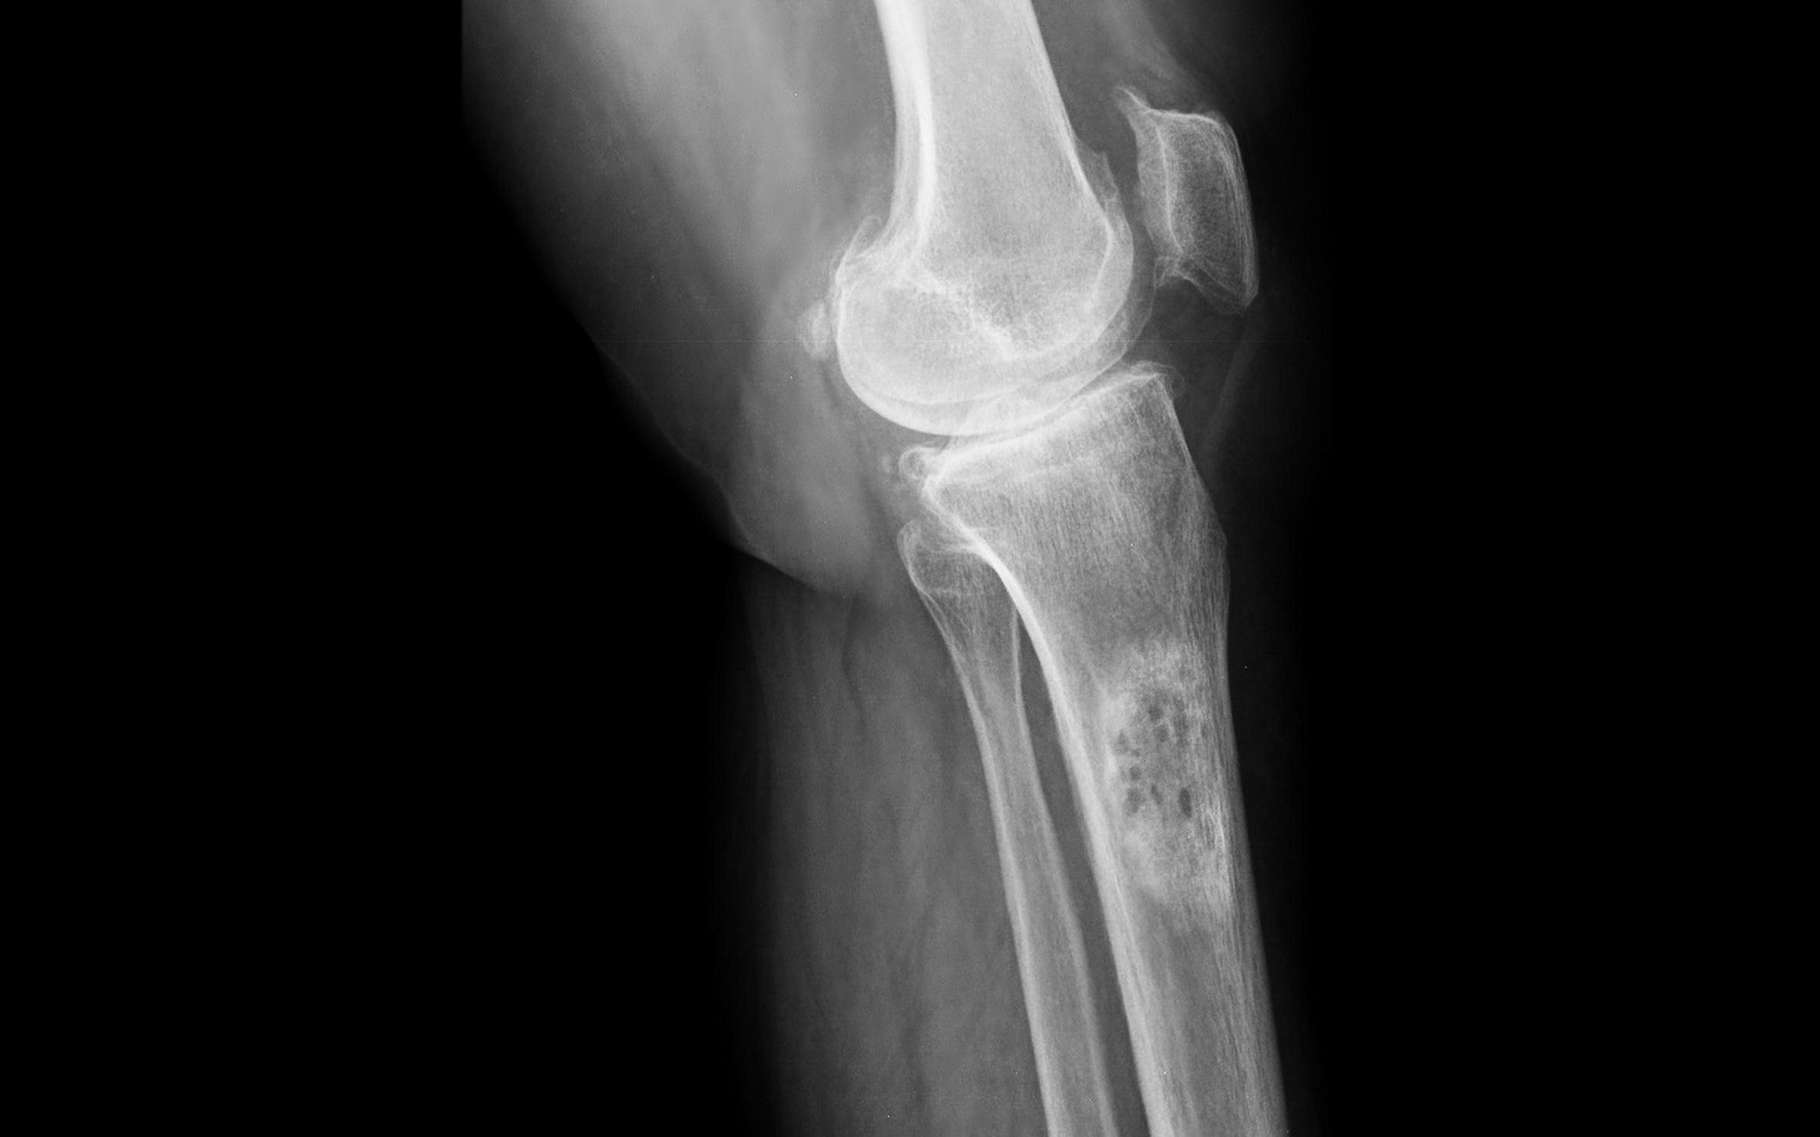

Cancer des os traitement naturel, nouveau, remède miracle, guérison